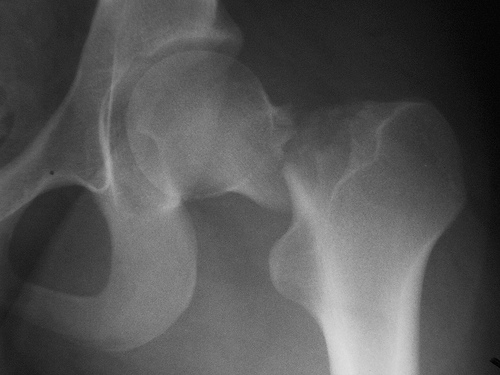

Benzodiacepinas y fracturas de cadera

El uso de benzodiacepinas se asoció a un aumento del riesgo de fractura de cadera en pacientes con y sin enfermedad de Alzheimer. JAMDA, 12 de noviembre de 2016

Fármacos y fracturas en los ancianos

Un estudio halló que más del 75% de los pacientes fracturados recibían fármacos que aumentan el riesgo de fractura. Además, la mayoría los siguió utilizando después. JAMA Internal Medicine, 22 de agosto de 2016